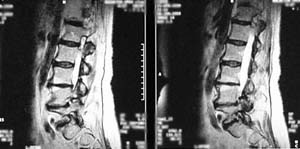

Lumbar spine MRI showing degenerated disc

Above: Sagittal (side view) lumbar MRI shows lumbar disc degeneration of the bottom 3 discs. Note the darkened color and loss of disc height suggesting disc desiccation (drying out). The taller, grey colored discs are more normal.